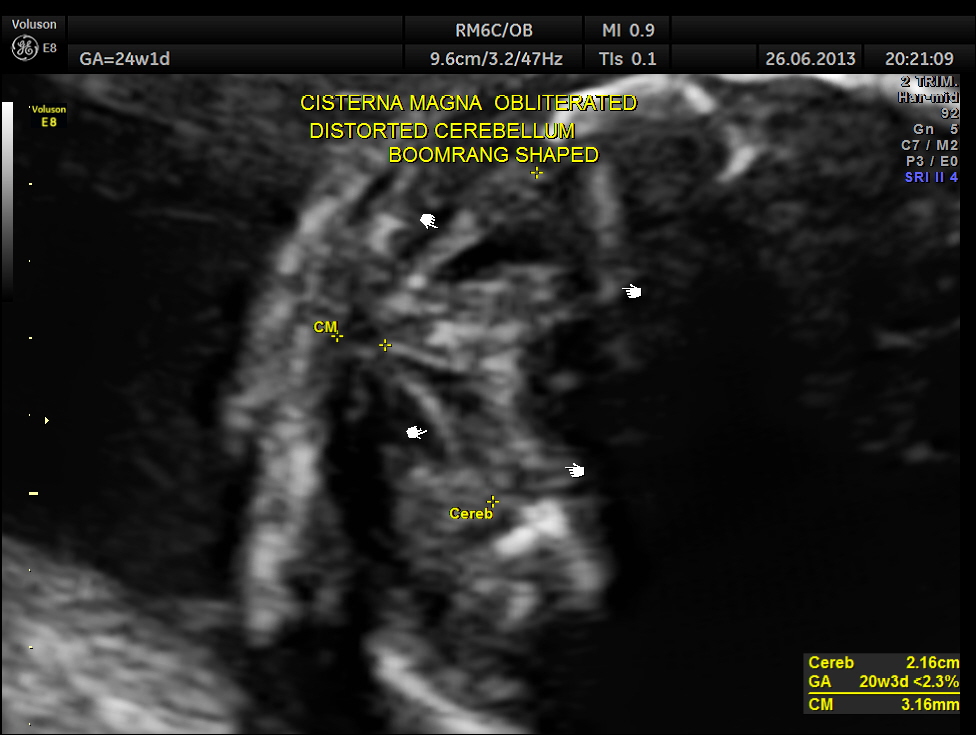

The cerebellum was distorted in shape – boomerang shaped and the cisterna magna was almost obliterated.